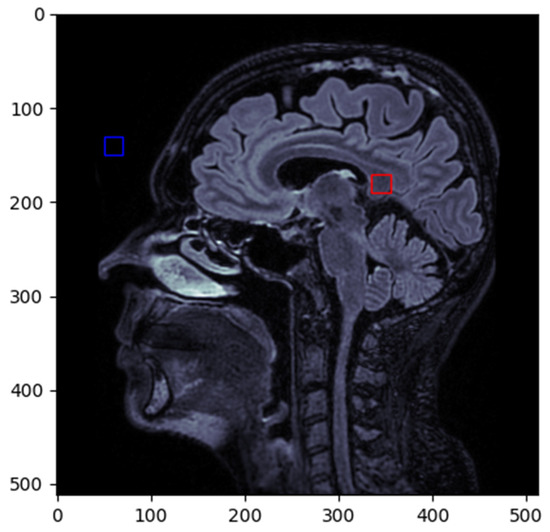

To calculate the SNR, we selected the splenium of the corpus callosum (red box) as the primary region of interest (ROI), and the noise was measured from the forehead region (blue box) (Figure 2).

Figure 2. ROI selected for SNR calculation.